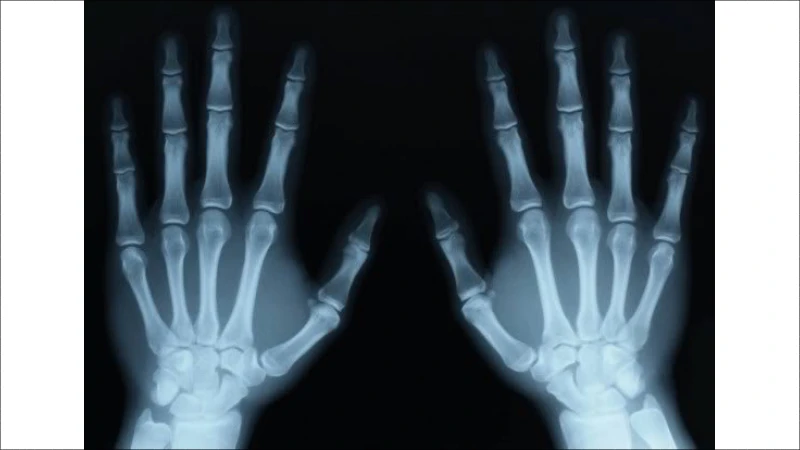

Để chẩn đoán chính xác, bác sĩ sẽ cần:

• Quan sát triệu chứng: Kiểm tra trực tiếp tình trạng khớp.

• Chụp X-Quang: Để đánh giá tình trạng sụn khớp và sự tổn thương.

• Xét nghiệm máu: Để loại trừ các bệnh lý khác như viêm khớp dạng thấp.